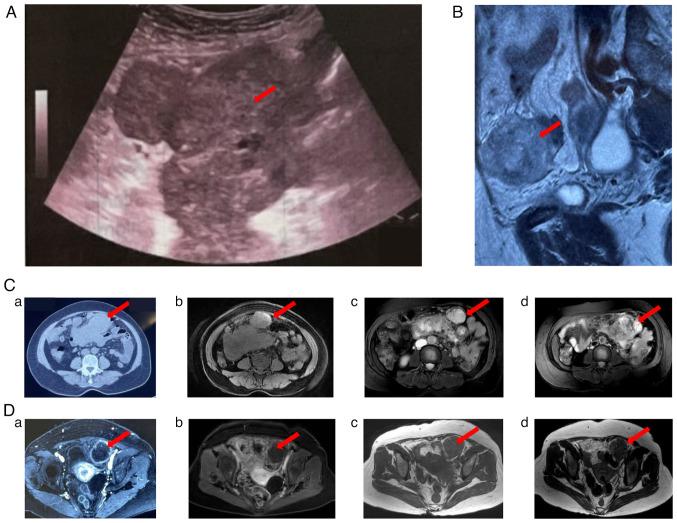

Primary diffuse malignant peritoneal mesothelioma (MPEM) is a malignant disease without standard treatments recommended. Recently, immunotherapy has revolutionized the field of tumor therapy. According to current clinical evidence, advanced MPEM may gain potential clinical benefits from immune checkpoint inhibitors. The present study reported a 61-year-old female patient with persistent low fever as the initial symptom, who was eventually diagnosed with MPEM. This patient obtained significant clinical benefits from pembrolizumab, with disappearance of symptoms, a lasting stable disease response with a progression-free survival of 10.0 months and a long overall survival of 26.2 months. The application of pembrolizumab was explored as an emerging effective treatment for patients with MPEM. In addition, the clinical characteristics, diagnosis, treatment, pathogenesis and target regulation in MPEM were discussed and previous studies were reviewed. Further evidence is needed from future extensive clinical trials.

原发性弥漫性恶性腹膜间皮瘤(MPEM)是一种尚无推荐标准治疗方法的恶性疾病。近年来,免疫疗法彻底改变了肿瘤治疗领域。根据目前的临床证据,晚期MPEM患者可能从免疫检查点抑制剂中获得潜在的临床益处。本研究报告了一名以持续低热为首发症状的61岁女性患者,最终被诊断为MPEM。该患者使用帕博利珠单抗后获得了显著的临床益处,症状消失,疾病持续稳定缓解,无进展生存期达10.0个月,总生存期长达26.2个月。本研究探讨了帕博利珠单抗作为MPEM患者一种新兴有效治疗方法的应用情况。此外,还讨论了MPEM的临床特征、诊断、治疗、发病机制和靶点调控,并对既往研究进行了综述。未来还需要更多广泛的临床试验提供进一步的证据。